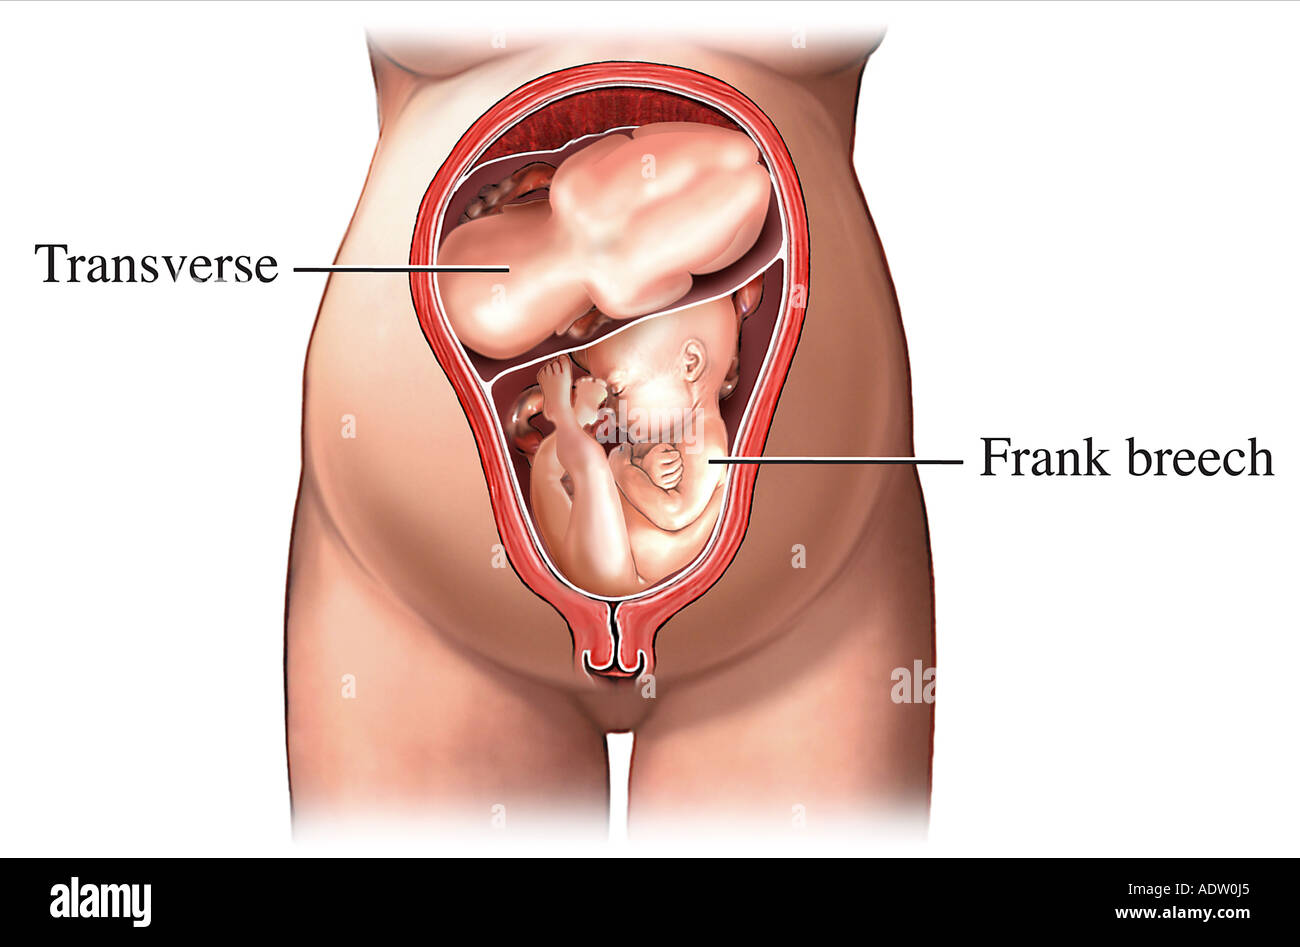

Breech.webp)

Живот с ягодичным предлежанием